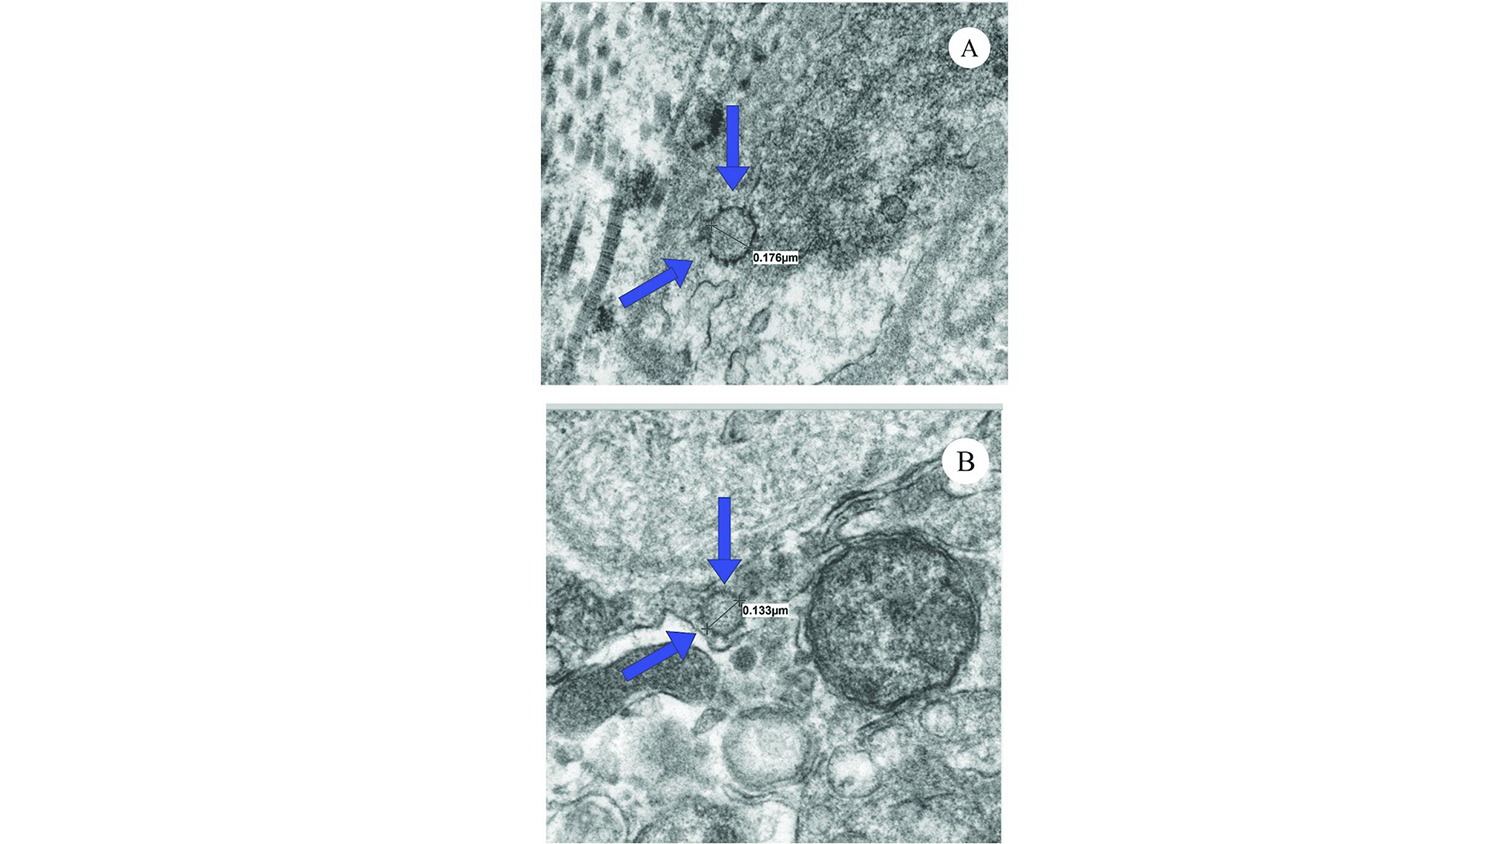

Рамасами и коллеги собрали образцы тканей полового члена у двух мужчин, которым пришлось пройти через фаллопротезирование, чтобы решить проблемы с эрекцией. Оба пациента перенесли COVID-19, один в легкой форме, другого же пришлось госпитализировать. Также исследователи взяли образцы тканей еще у двух мужчин с эректильной дисфункцией, но не болевших COVID-19. Возраст пациентов составил 65-71 год.

В пробах, полученных от переболевших мужчин, все еще определялись следы вирусной РНК, хотя мужчины выздоровели более полугода назад и анализ на COVID-19, проведенный перед операцией, был отрицательным.

Кроме того, у них наблюдались признаки эндотелиальной дисфункции. У мужчин из контрольной группы ее не было.